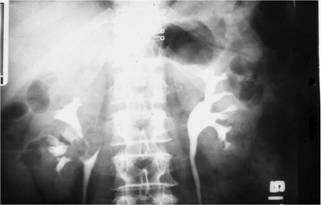

本題的解題核心在於辨識靜脈注射尿路X光攝影(IVU)中,左側腎盂內不規則的「填充缺損」(filling defect),結合病人肉眼可見血尿的症狀,指向泌尿道上皮細胞癌。